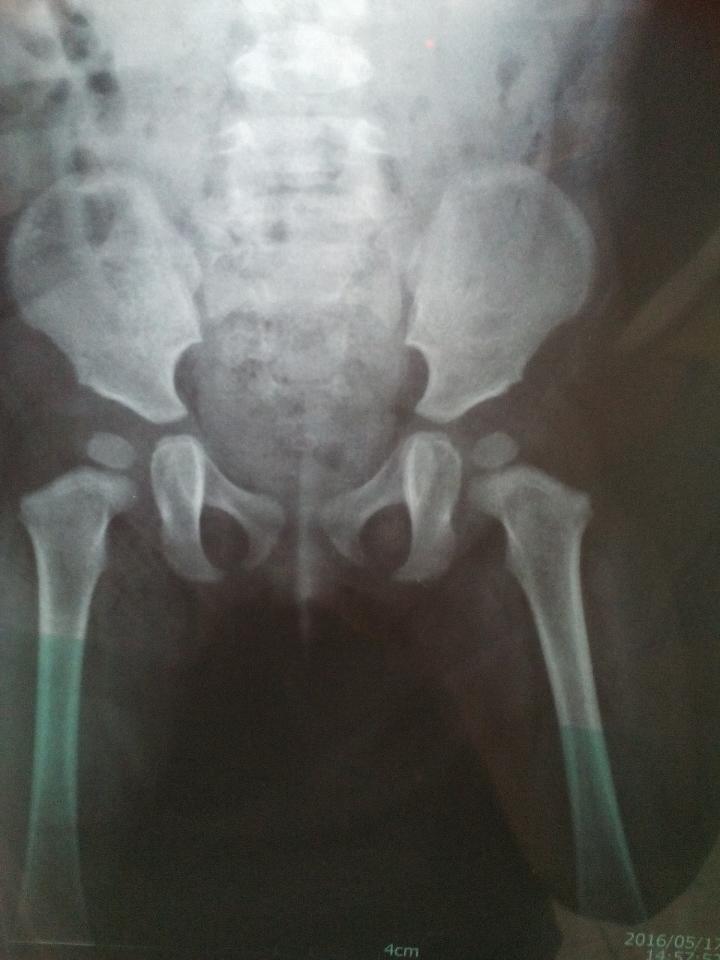

麻烦能看董片子的骨科大夫给看看片子 谢谢了 麻烦能看董片子的骨科大夫给看看片子。谢谢了。 点击展开 冉磊宝贝 2016-07-01 22:47 为您推荐: 其他回答 祝宝宝健康 白露为霜晶莹 2016-07-01 23:20 问医生……… 家里有三个小棉袄 2016-07-01 23:06 。。。??? 泡沫之夏1234 2016-07-01 22:50 问问医生。 卷卷┳━┳ノ(°_°ノ) 2016-07-01 22:48 相关问题 急急急,麻烦小儿骨科大夫帮我看看片子,如何更能合适的治疗小孩? 急急急,麻烦小儿骨科的大夫帮我看看片子,如何合适的为小儿的粉碎性骨折做出更适合的治疗,非常感谢! 麻烦骨科大夫和妇产科大夫给个建议